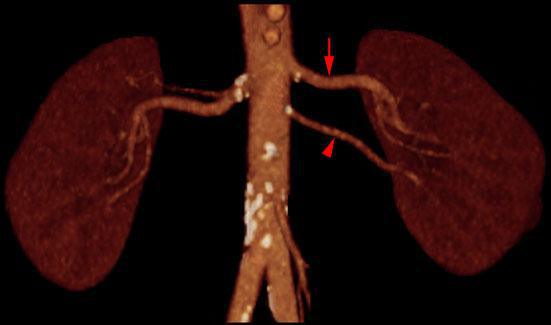

Hipernefroma 2